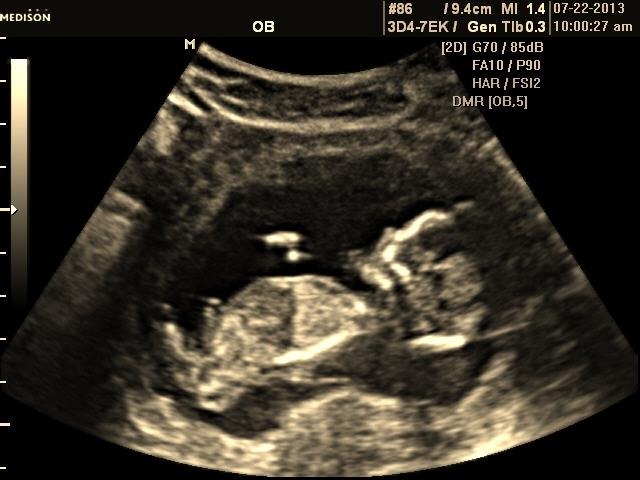

My little sister just had her u/s today..she is 13 weeks 6 days. Any guesses would be appreciated! Thank you all!Attachment 12505Attachment 12506Attachment 12507Attachment 12508

I *think* there is a boyish nub on the second picture. Only prob is that baby is pretty arched. I would go 60-40 boy.

Not sure there is a nub, but if what I am looking at is a hint of a nub I am thinking boy

guessing girl based on the third photo :)